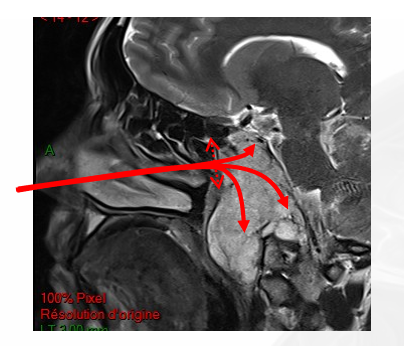

一位48岁的女士确诊为斜坡脊索瘤,外展神经麻痹,看东西时常常出现斜视和复视,因为复视走路也不稳……肿瘤侵袭广泛,已经延伸到了岩尖、海绵窦、颈静脉孔等部位,直至硬膜内。位置深,侵袭范围广,安全全切不易。

没想到这种复杂的情况,福教授并没有开颅,而是经鼻内镜手术。福教授不仅需要尽力全切肿瘤,还要进行颅底重建以避免脑脊液漏。为了减少经鼻内镜手术和颅底重建技术的并发症风险,需要一种新的手术替代策略,以尽量减少正常组织的切除,而福教授的鼻粘膜修复技术能够很好地适用于该患者。

最终手术顺利完成,术后 MRI 证实肿瘤被完全切除(箭头所指为填充的脂肪),同时鼻窝保持完整。在2个月的随访中,内镜检查没有发现结痂,患者也没有抱怨任何鼻腔不适。